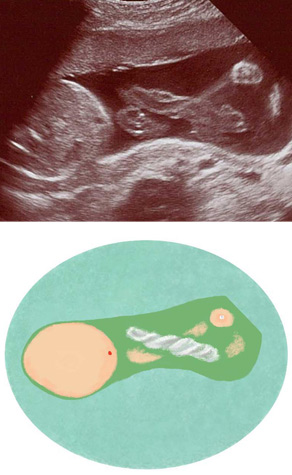

妊娠25週ころの超音波写真

へその緒も太く成長しています

中央に見えるのはへその緒です。血管は見えませんが、コラーゲン組織のよじれがくっきり写っています。成長するにつれ、へその緒は太くなりますが、長さと太さには個人差があります。